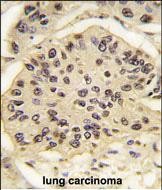

Formalin-fixed and paraffin-embedded human lung carcinoma tissue reacted with SOX2 Antibody , which was peroxidase-conjugated to the secondary antibody, followed by DAB staining. This data demonstrates the use of this antibody for immunohistochemistry; clinical relevance has not been evaluated. |